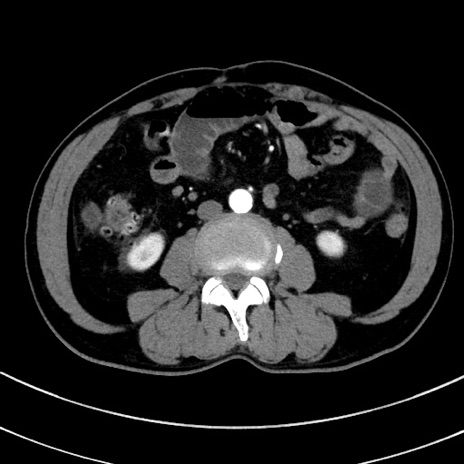

症例8(横断像)

【症例】 60歳代男性

【主訴】 黒色吐物

【現病歴】 4日前から嘔気自覚、2日前の朝食後にも嘔気あり、自分で手で嘔吐反射起こし嘔吐したところ血が混ざっていたため受診。

【既往歴】 5年前汎発性腹膜炎を伴う急性虫垂炎で手術、高血圧、前立腺肥大症、高脂血症

【身体所見】 腹部正中に手術癩痕あり 腹部平坦・軟圧痛なし膨満感あり

【データ】WBC 8400、CRP 4.54